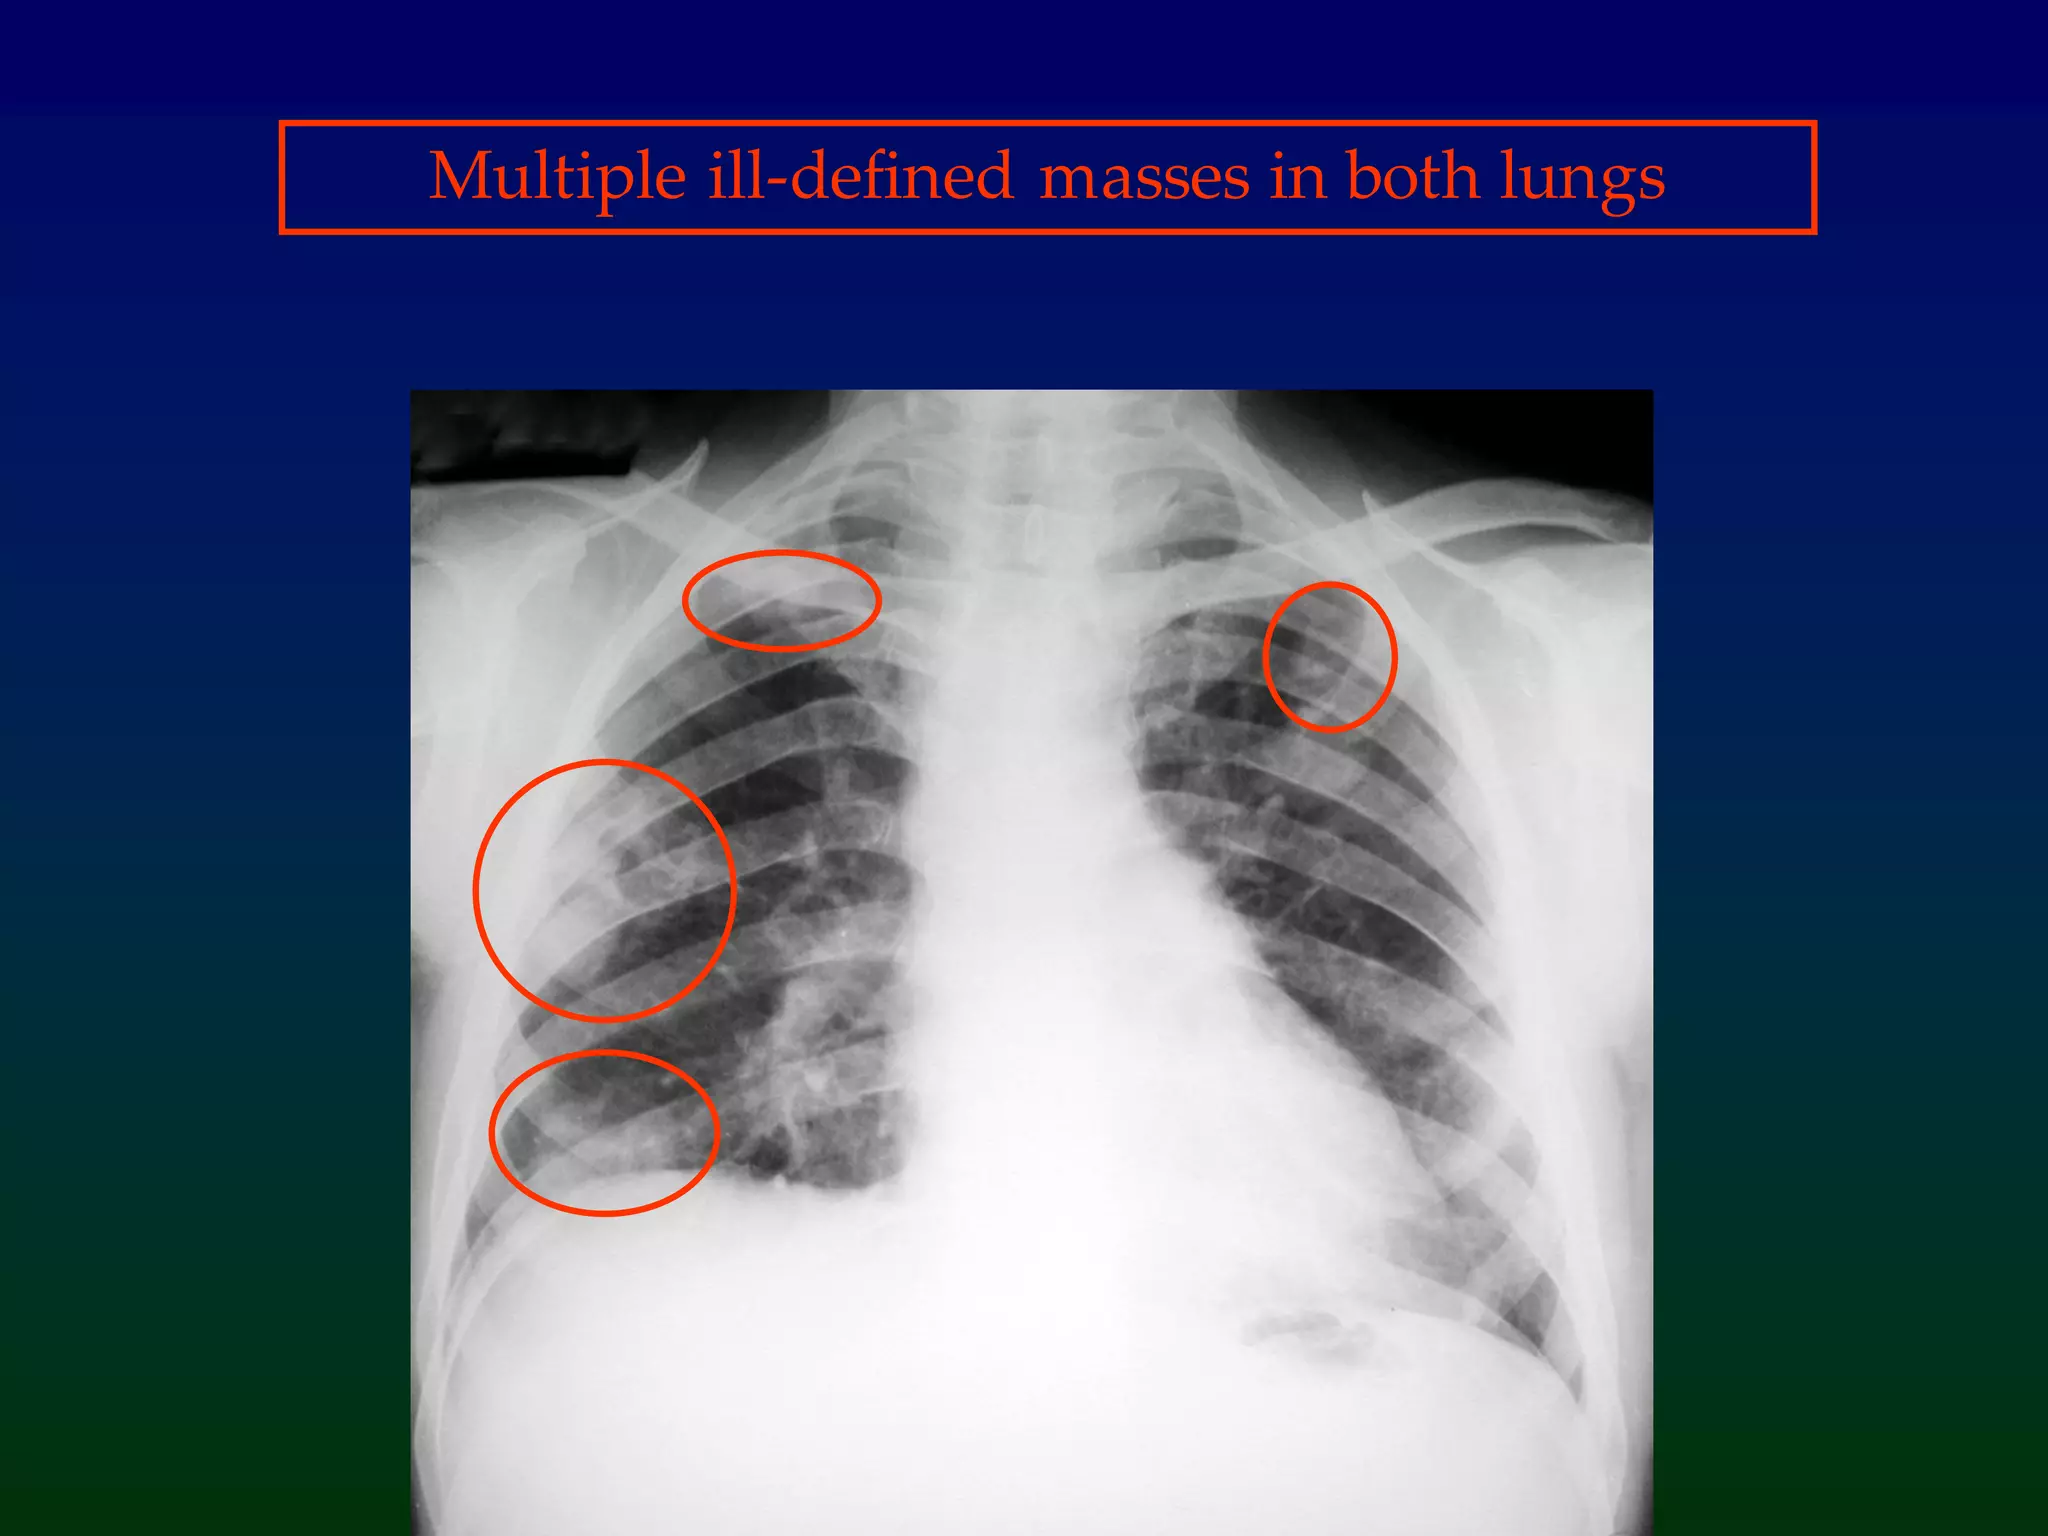

Multiple ill-defined masses in both lungs

Diagnosis = Septic emboli=Multiple cavitating lung

abscesses in a intravenous drug user

A 19 year old unemployed

male is admitted to AMAU

with breathlessless and fever.

He has venepuncture wounds

on his arms.

Look at his CXR on the next slide. Try to workout

what the diagnosisis.